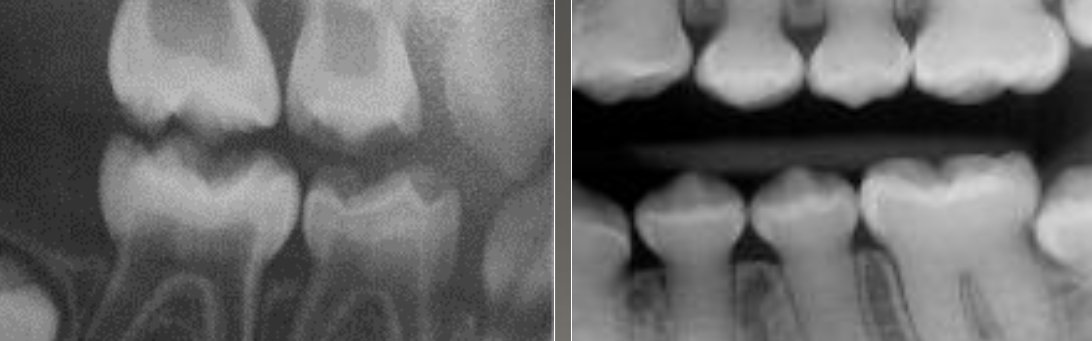

DGI radiographic presentation

bulbous crown, cervical constriction, pulp obliteration varies, expanded pulp = shell teeth

4 types, normal clinical crown, short roots, periapical radiolucencies, chevron pulp chambers

DD-I

have a blue-amber-brown translucence, bulbous crown, cervical constriction, thin roots, normal length, early obliteration of pulp

DD-II primary teeth

have a normal color clinically, pulp chamber is enlarged = thistle tube or flame shaped, pulp stone, normal root

DD-II permanent teeth